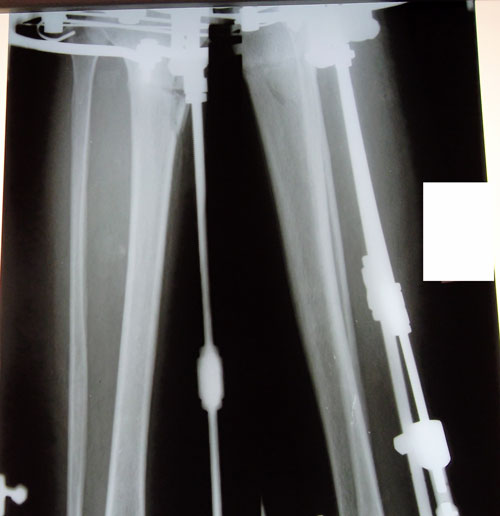

Дата операции 11.02.2014г.

Дата снятия аппаратов 16.05.2014г.

Срок лечения 95 дней.